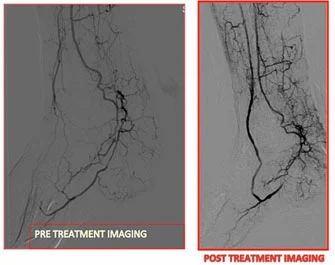

Molti pazienti, pur non avendo mai subito una lesione evidente al piede, presentano complicanze neuro-vascolari che li pongono a rischio di sviluppare il piede diabetico. Nel tempo, la definizione di piede diabetico si è ampliata, comprendendo tutte le “alterazioni anatomo-funzionali causate dall’arteriopatia occlusiva periferica e/o dalla neuropatia diabetica”, fattori che compromettono la salute e la funzionalità degli arti inferiori.

Questo approccio evidenzia l’importanza di un monitoraggio continuo e di un trattamento precoce per evitare gravi complicanze.